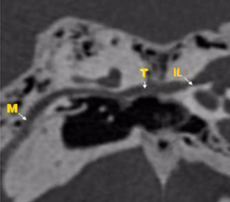

Figura 7. Reconstrucción de trayecto del nervio facial de un oído derecho: Segmento mastoideo (M), Timpánico (T), Intralaberintico (IL) |

Relación del nervio facial con la ventana oval.

El prolapso y la dehiscencia del nervio facial son la segunda causa de disminución del calibre del nicho de la ventana oval. Un nervio facial dehiscente puede dificultar o incluso impedir la realización de una estapedectomía o de una estapedectomía o estapedotomía (Fig. 7).